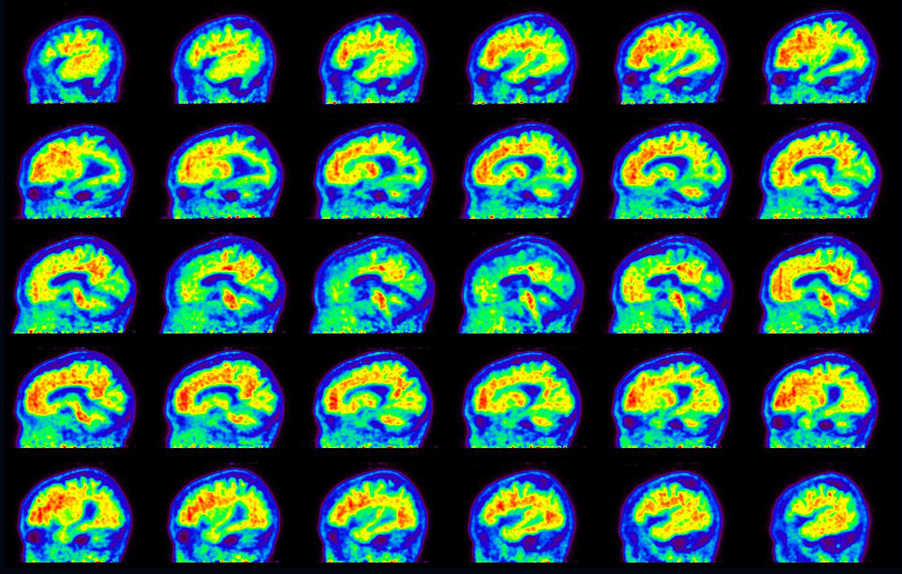

Sagittal